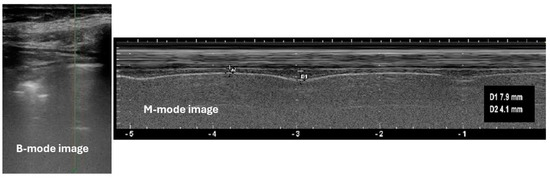

3.2. Technique of Diaphragm Assessment by Ultrasound